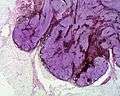

Micrograph of a blue nevus showing the characteristic pigmented melanocytes between bundles of collagen. H&E stain. | |

Blue nevus (also known as "blue neuronevus," "dermal melanocytoma," and "nevus bleu"[1]) is a type of melanocytic nevus. The blue colour is caused by the pigment being deeper in the skin than in ordinary nevi. In principle they are harmless[2] but they can sometimes be mimicked by malignant lesions, i.e. some melanomas can look like a blue nevus.[3][4]